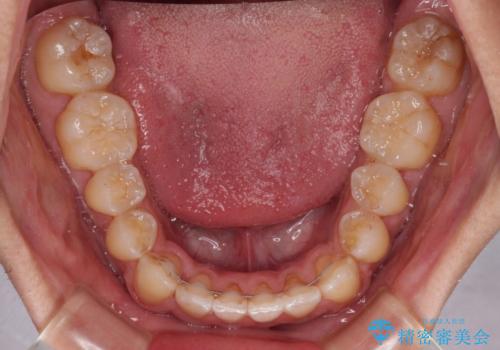

- 前歯のデコボコを気にして来院された患者様です。

歯列としてはワイヤー装置でもインビザラインでも対応可能でしたが、インビザラインが苦手とする上顎側切歯(真ん中から2番目の歯)の舌側転位が顕著でした。

治療の確実性を上げるために、インビザライン開始前に上顎のワイヤー装置にて舌側転位を解消し、その後インビザラインにて矯正治療を行うこととしました。

前歯のデコボコが早めに改善され、スムーズに治療を終えることができました。